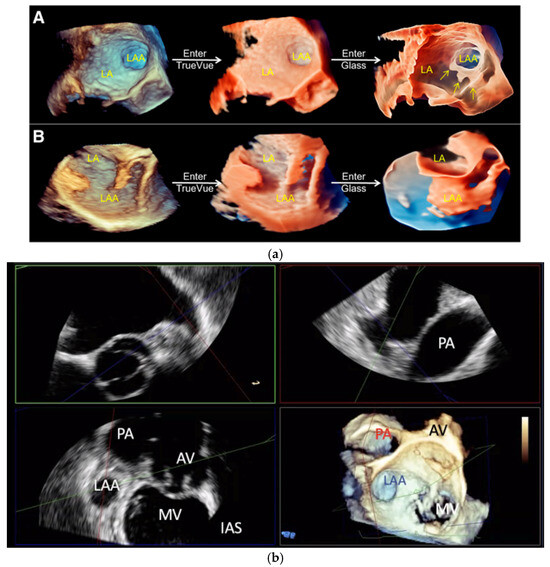

- Sun, A.; Ren, S.; Xiao, Y.; Chen, Y.; Wang, N.; Li, C.; Tan, X.; Pan, Y.; Sun, F.; Ren, W. Real-Time 3D Echocardiographic Transilluminated Imaging Combined with Artificially Intelligent Left Atrial Appendage Measurement for Atrial Fibrillation Interventional Procedures. Front. Physiol. 2022, 13, 1043551. [Google Scholar] [CrossRef]